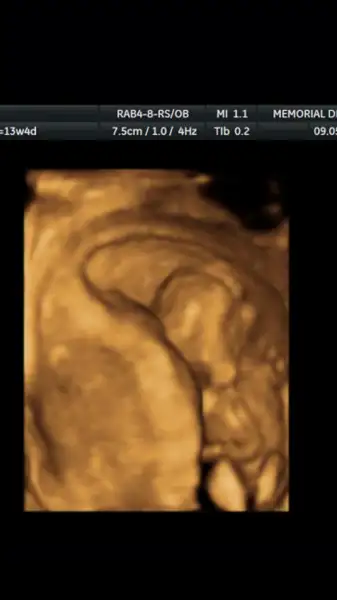

EderimEki Görüntüle 1993062 Bebegimin 11.4 gunluk ultrason görüntüsüne göre bilen varsa tahmin edebilirmisnz. Yarin da doktora gidecegim ama genelde bu sekilde duruyor. Sakliyor.

Kızlar ikinci resim de 12.4 gunluk renkli ultrason. Videodan aldim. Cok net degil. Bir saniyeligine açıyor sanki